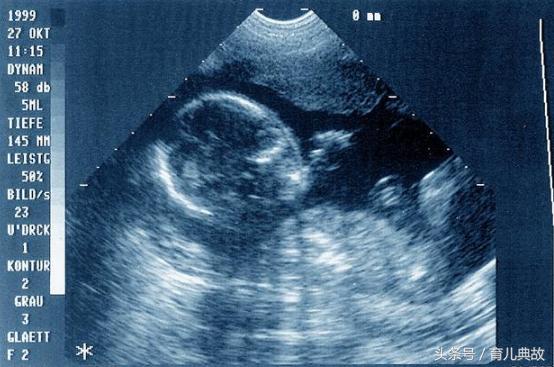

胎心监护其实是一个很简单的检查项目,一般时间在20分钟左右,对准妈妈没有任何损伤,所以不用担心。做胎心监护时,准妈妈们坐在椅子上或者半卧姿势,用一两根带子将仪器固定在肚子上,然后护士启动仪器,进行监测即可。

图片来自网络